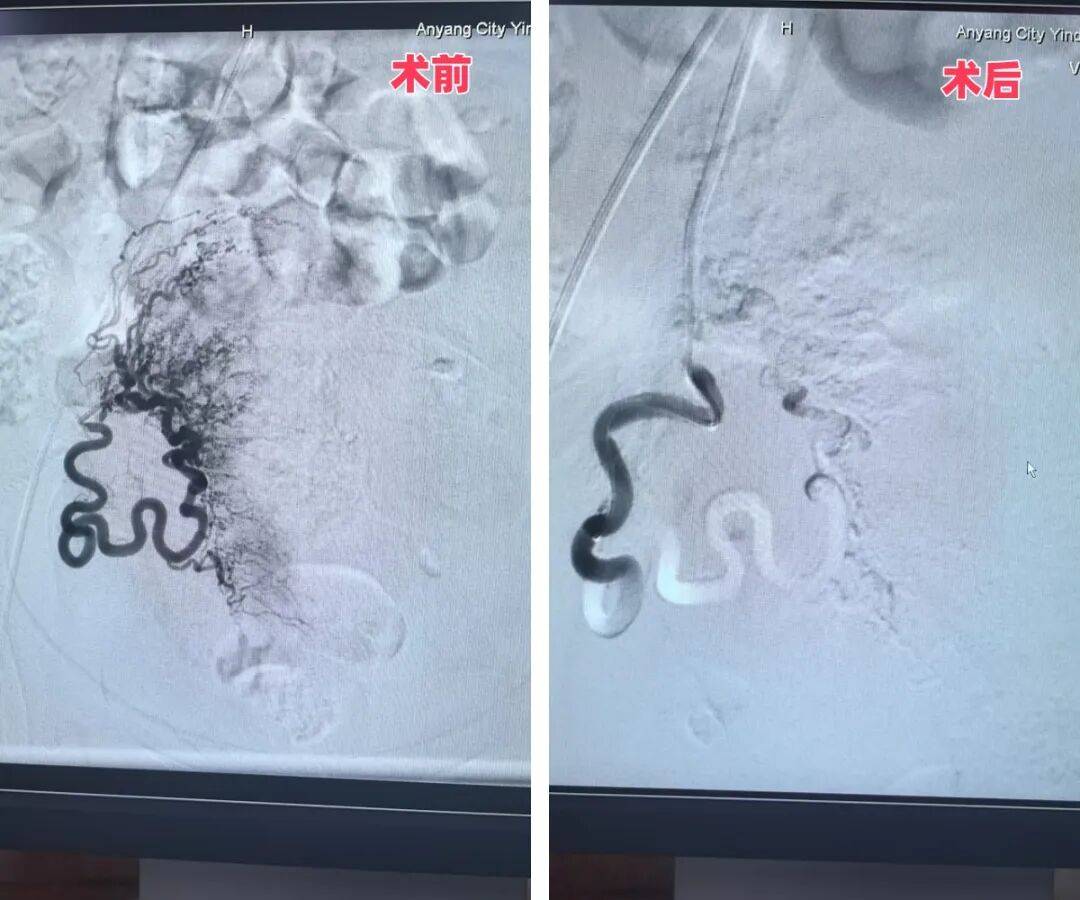

1月31日,殷都區(qū)人民醫(yī)院院長、介入專家魏棟親自操刀實(shí)施手術(shù)。憑借多年積累的豐富臨床經(jīng)驗,魏院長精準(zhǔn)完成雙側(cè)子宮動脈栓塞操作,全程過程順利、定位精準(zhǔn),成功為患者筑起“止血防線”,大幅降低了后續(xù)手術(shù)的出血風(fēng)險。此次雙側(cè)子宮動脈栓塞術(shù),是殷都區(qū)人民醫(yī)院首次將介入技術(shù)應(yīng)用于婦科手術(shù),實(shí)現(xiàn)了相關(guān)診療領(lǐng)域的“零突破”。

左側(cè)子宮動脈手術(shù)前后對比圖

右側(cè)子宮動脈手術(shù)前后對比圖